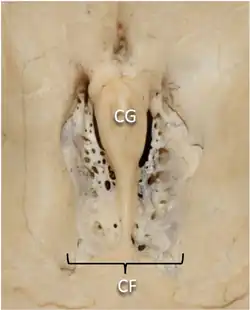

Superior view of the central part of the anterior cranial fossa.

CG: crista galli; CF: cribriform plate | |